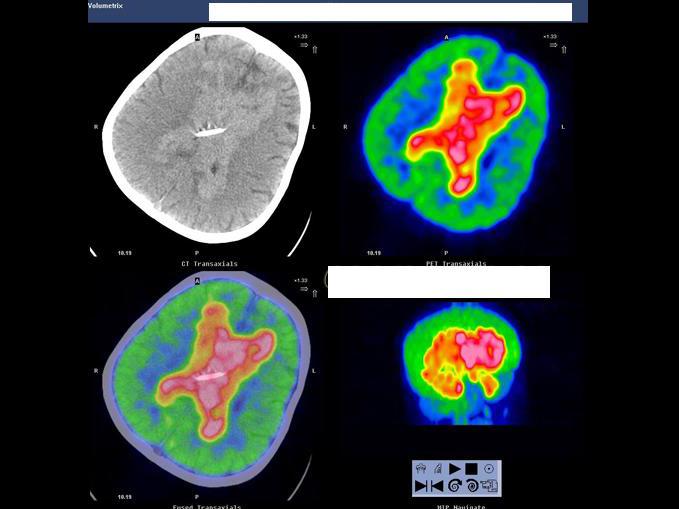

[单选题]男,7岁,2岁时因头痛而就诊,MRI示脑积水、颅内(小脑蚓部及蝶鞍)见多发恶性肿瘤,临床诊断为髓母细胞瘤。未行手术治疗,多年来一直行放、化疗治疗,最后一次化疗1个月前结束。因腹胀、恶心、呕吐1周而就诊,CT示:双侧侧脑室充满肿瘤病灶,PET/CT全身显像如图。正确的描述是 ( )A.肿瘤复发并沿双侧侧脑室弥漫性浸润B.肿瘤同时向双侧丘脑及豆状核浸润、侵犯;蝶鞍内块状高代谢病灶,考虑为转移灶C.脑干及颈段、胸段、上腰段脊髓内见长条状高代谢病灶,考虑为肿瘤向脑干及大部分脊髓播散、种植转移D.正常情况

[多选题] 男,7岁,2岁时因头痛而就诊,MRI示脑积水、颅内(小脑蚓部及蝶鞍)见多发恶性肿瘤,临床诊断为髓母细胞瘤。未行手术治疗,多年来一直行放、化疗治疗,最后一次化疗1个月前结束。因腹胀、恶心、呕吐1周而就诊,CT示:双侧侧脑室充满肿瘤病灶,PET/CT全身显像如图。正确的描述是()。A . 肿瘤复发并沿双侧侧脑室弥漫性浸润B . 肿瘤同时向双侧丘脑及豆状核浸润、侵犯;蝶鞍内块状高代谢病灶,考虑为转移灶C . 脑干及颈段、胸段、上腰段脊髓内见长条状高代谢病灶,考虑为肿瘤向脑干及大部分脊髓播散、种植转移

A.肿瘤复发并沿双侧侧脑室弥漫性浸润

B.肿瘤同时向双侧丘脑及豆状核浸润、侵犯;蝶鞍内块状高代谢病灶,考虑为转移灶

C.脑干及颈段、胸段、上腰段脊髓内见长条状高代谢病灶,考虑为肿瘤向脑干及大部分脊髓播散、种植转移

D.正常情况下脊髓内无明显放射性浓聚,当出现椎管内肿瘤转移则可表现为

F-FDG明显浓聚,呈“辫子征”